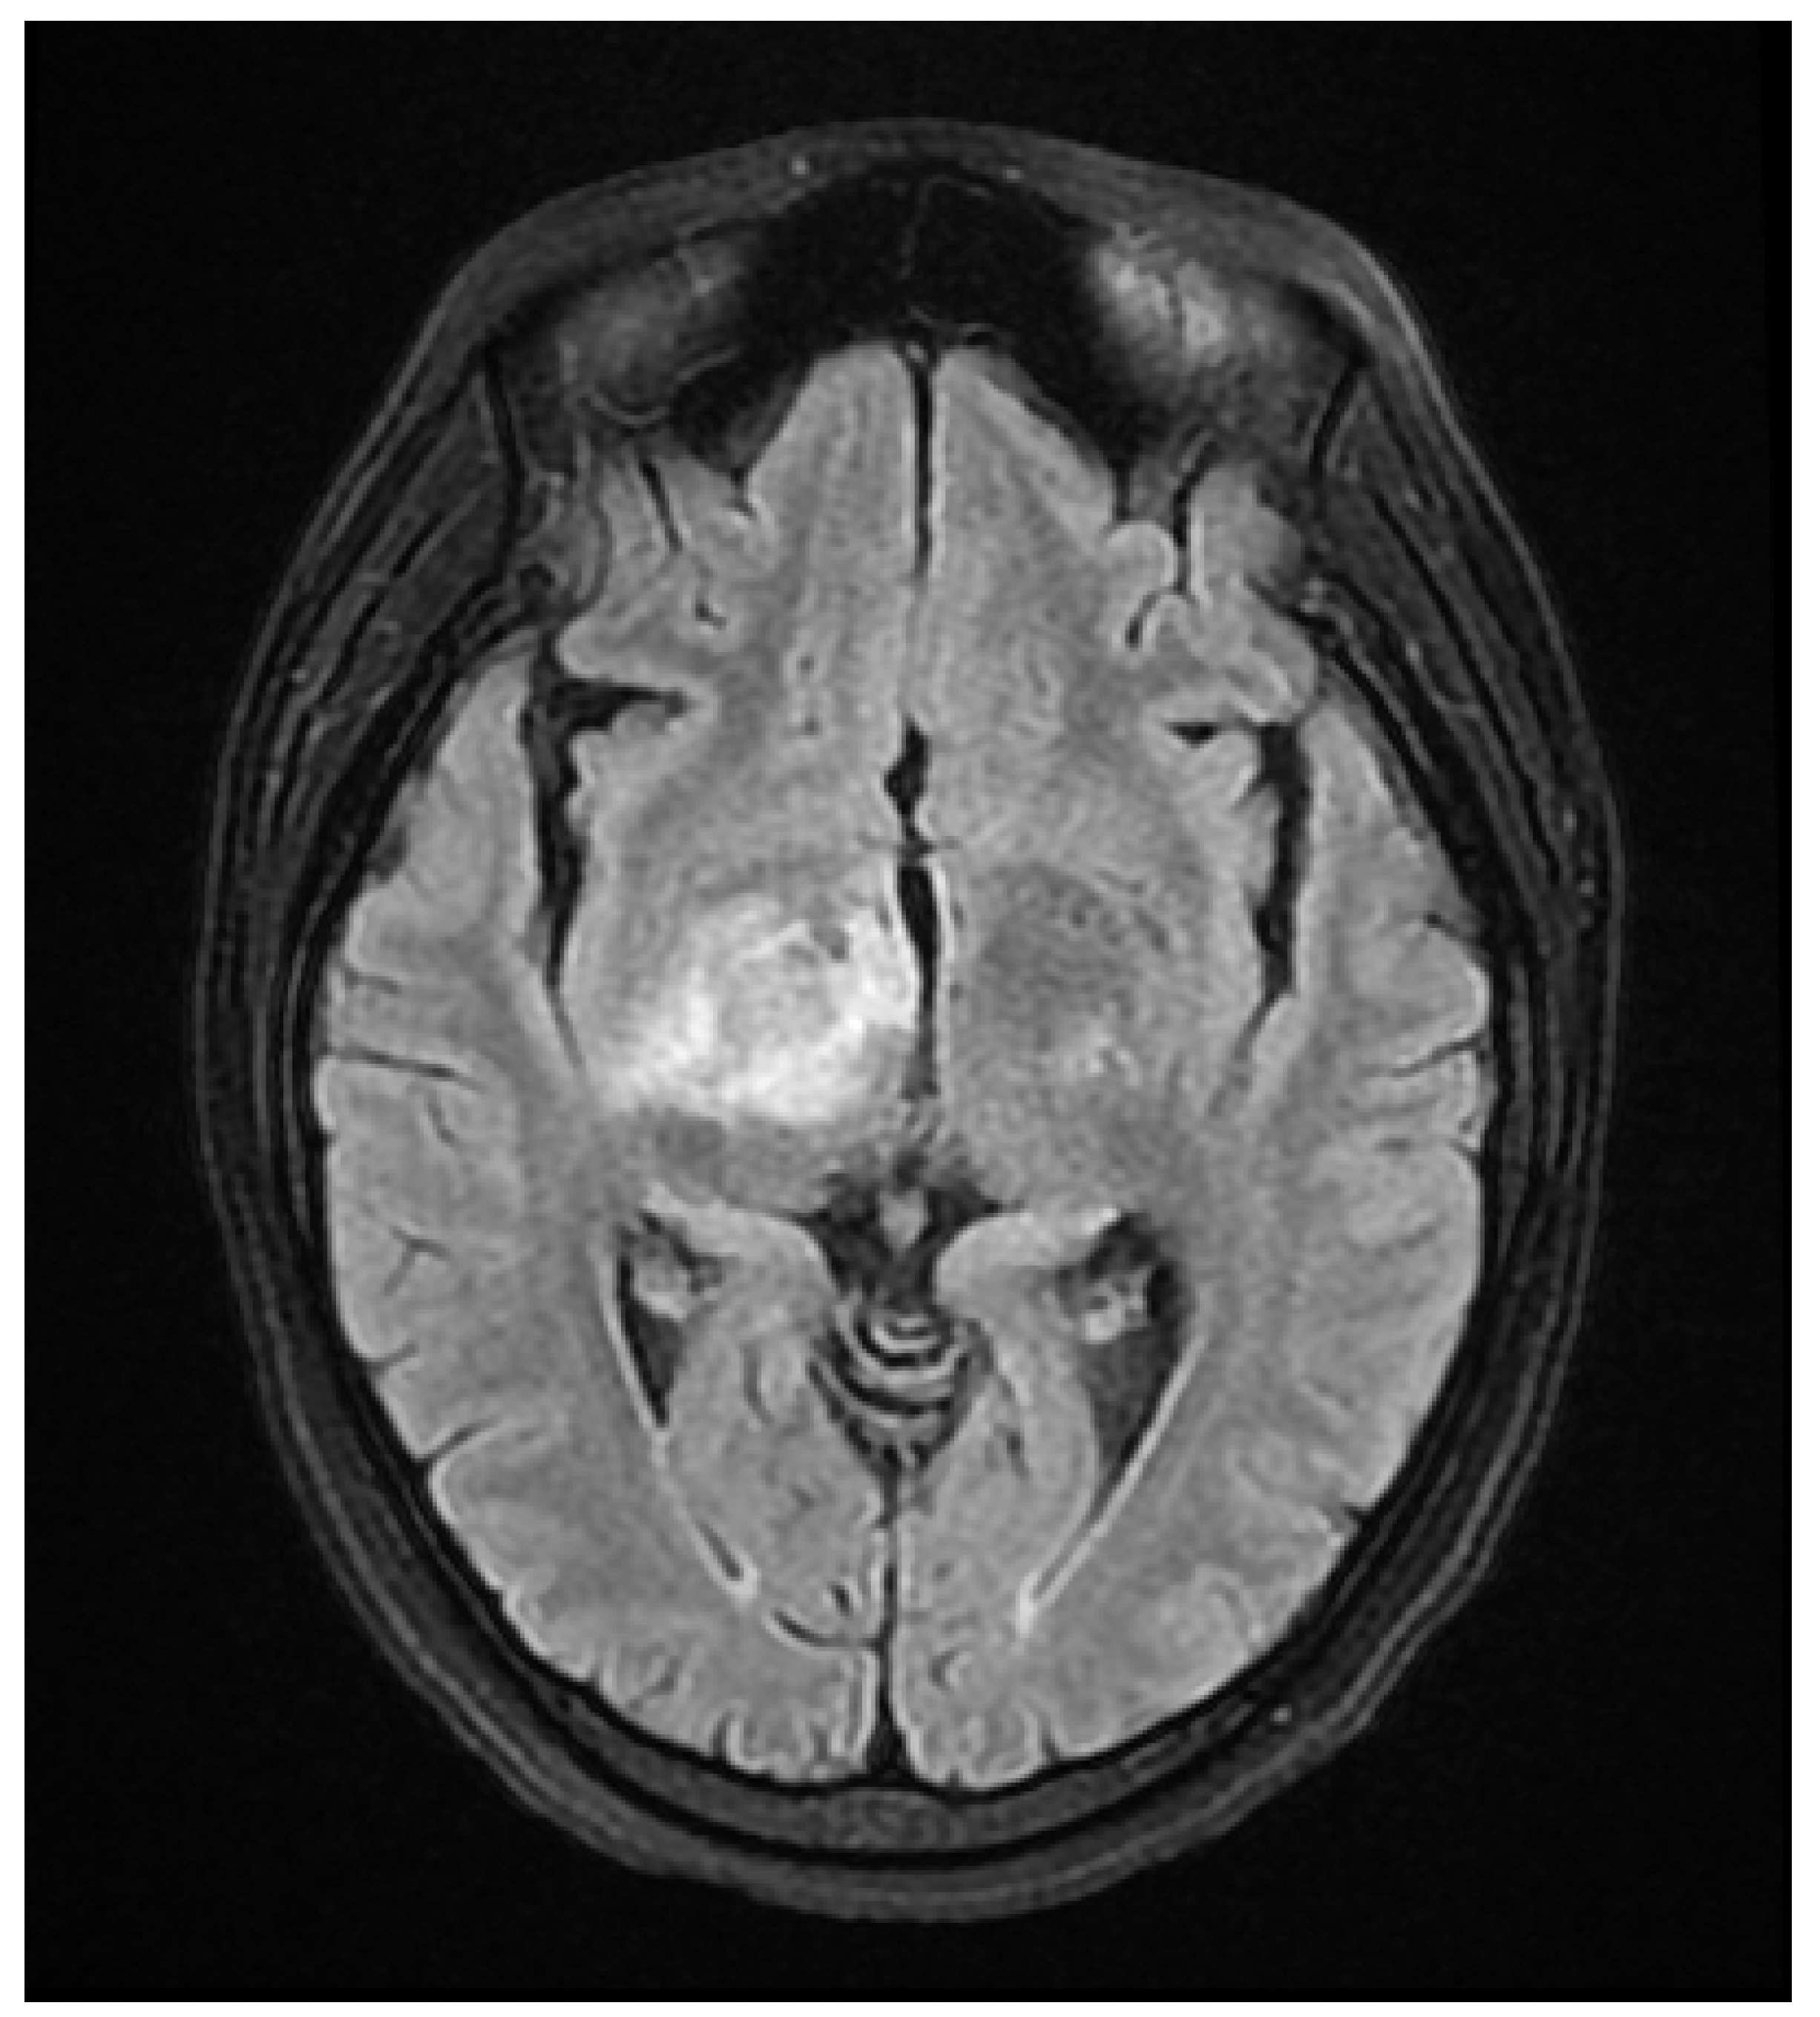

A 37 year old female presented to our hospital due to new onset severe headaches and right sided weakness with facial droop. The patient did not have any significant past medical history before this point. Patient was unable to speak properly and was found to have decreased responsiveness at bedside. Initial CT scan of the head without contrast revealed ill-defined edema involving the left periatrial white matter, involving the central gray matter and external limited internal capsule. MRI head with T2 Flair revealed diffuse edema and inflammation throughout the brainstem, pons, midbrain, and basal ganglia (Figure 1, Figure 2, Figure 3 and Figure 4). EEG showed diffuse slowing suggestive of moderate diffuse cerebral dysfunction without evidence of seizures or epileptiform activity. Lumbar puncture demonstrated a normal opening pressure, with CSF containing 2 red blood cells, 9 white blood cells of which 94% were lymphocytes, glucose of 58, and protein of 42. CSF bacterial cultures were negative, along with no evidence of active HSV or EBV infection. RPR was also negative. Pulse dose steroids were initiated in the ICU. Patient was slow to improve and was transferred to the neurological intensive care unit for further management. After 17 days in the ICU patient was discharged to a rehabilitation facility. Patient slowly improved with physical therapy but did continue to have some refractory lower extremity weakness. At the time of discharge, our patient was discharged on 20mg prednisone daily. Outpatient brain biopsy of the right frontal cortex revealed moderate gliosis but no abnormal lymphocytic infiltration. After thorough review of imaging findings and clinical presentation a diagnosis of acute disseminated encephalomyelitis was made by Neurology.

Figure 2. Flair Axial MRI image reveals white matter lesions in the midbrain.